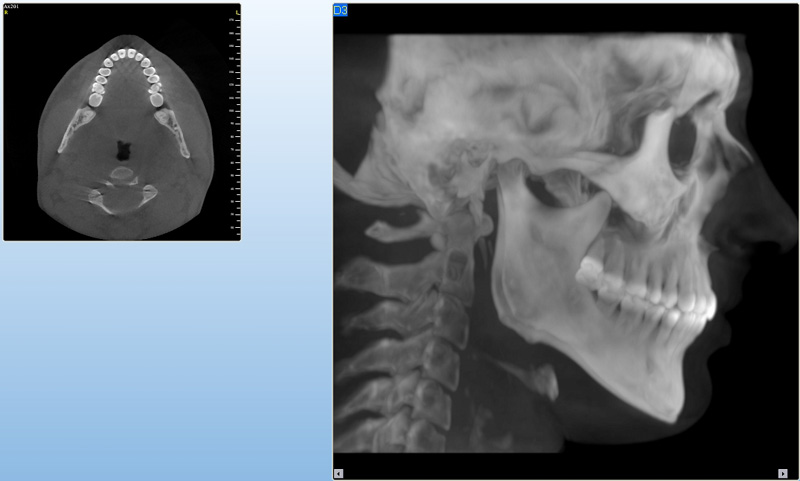

NewTom Giano

Jedná se o nejnovějším přístroj ze skupiny dentálních hybridních CBCT (3D) + 2D (pan i ceph) systémů. Opět umožňuje na základě jediného snímkování vytvořit všechny typy RTG zobrazení, které jsou pro lékaře potřebné. Používaná technologii tzv. „kuželového paprsku“ a speciální senzory pro minimální zátěž při snímkování pacienta.

Vyšetření pomocí tohoto přístroje (nebo

3D DVT - NewTom) a získaná data používáme

pro každou implantaci, dále ve stomatochirurgii (zlomeniny čelistí, zuby moudrosti, cysty, onemocnění čelistního kloubu), ortodoncii (retinované zuby, nadpočetné zuby), parodontologii atd.